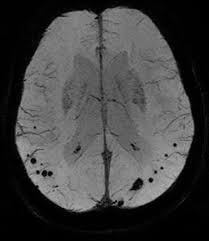

I am sharing the results of a study involving middle-aged and older adult patients with obstructive sleep apnea (OSA) in which those with moderate to severe OSA had a higher risk of developing cerebral microbleeds compared to the group without OSA during an 8-year follow-up period. This finding suggests that moderate to severe OSA could be an independent risk factor associated with the development of cerebral microbleeds in the general adult population.